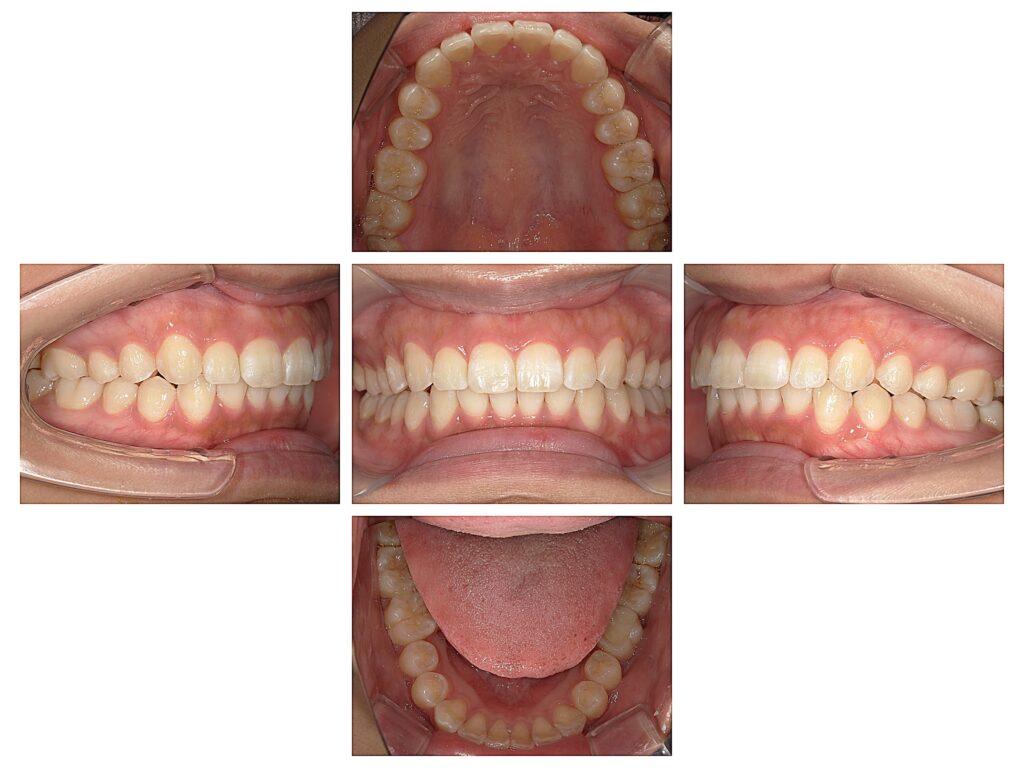

↑部分矯正装置インビザラインGoをおこなった患者様です。

前歯の重なりと上前歯が少し出ているのが気になるとのことでした。

約5か月間でキレイな前歯になりました✨

◎治療装置:インビザライン Go (部分矯正)

矯正装置費用:¥385,000(税込み)

治療期間:約5ヶ月 (保定期間は別)

(アライナー使用枚数 9枚+追加アライナー 4枚)

治療に際し予想される副作用:

・矯正治療による歯の痛み

・矯正装置装着中の発音障害

・矯正装置に対するアレルギー症状

・歯肉退縮 ・歯根吸収 等